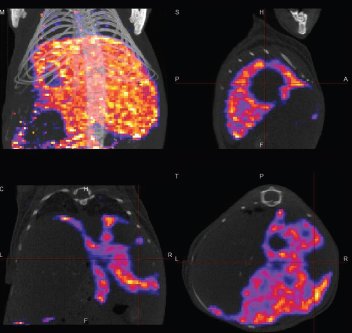

Das voll integrierte CT bietet niedrige Dosis mit Scanfunktionen (80 um und 160μm Pixelgröße) und Zykluszeiten von ~ 40-60 Sek. für eine Maus und 1-2 min. für eine Ratte. Das CT wird für die 3D-SPECT-oder PET-Field of View-Auswahl über eine patentierte einfache grafische Schnittstelle verwendet. Automatische, markierungsfreie Fusion von 3D SPECT- oder 3D-PET-Bilder mit 3D-Röntgen-CT-Bildern ist ein Standard-Feature bei U-SPECT-II / CT und Vektor / CT.